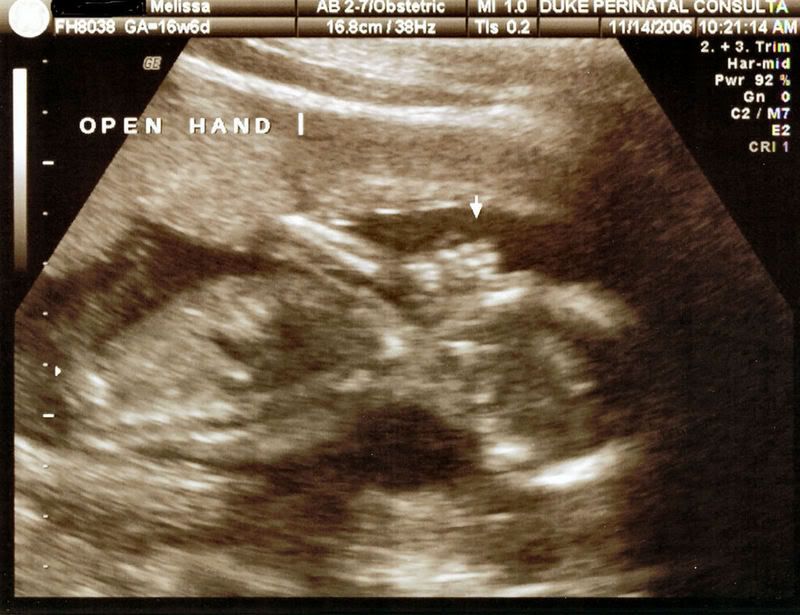

My daughter had her 18 week ultrasound today and we have a little boy. He was quite proud to display his little tallywhacker at the appropriate moment. We are so thrilled and tickled that he seems very happy and healthy. As soon as I get the pictures loaded onto photo bucket I will post the handsome little devils pictures. |

here he is asleep http://i11.photobucket.com/albums/a190/the...b4fan/Sleep.jpg from the side with his little hand open http://i11.photobucket.com/albums/a190/the...an/openhand.jpg Here is his little face http://i11.photobucket.com/albums/a190/the...4fan/Face-1.jpg He had ginormous feet http://i11.photobucket.com/albums/a190/the...ab4fan/Foot.jpg His defining moment http://i11.photobucket.com/albums/a190/the...fab4fan/Boy.jpg |